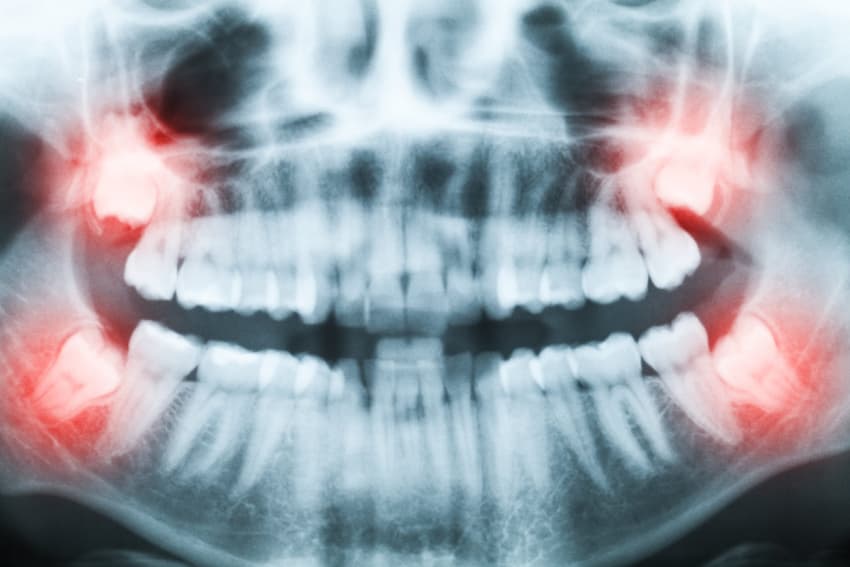

In many cases, wisdom teeth don't have enough space to properly erupt. Lower wisdom teeth, in particular, must "squeeze" between 2nd molars in front of them and dense jawbone behind them. To make things worse, the lower jaw curves upward dramatically in the area of the wisdom teeth (see x-ray above near the red illumination). For most people, their 3rd molars are "stuck" in a partially erupted position. In this position, only a small portion of the tooth is visible through the gums. The rest of the tooth is often submerged under the gums and surrounded by deep gum pockets that collect harmful food, plaque and bacteria. This places the patient at an increased risk of tooth decay and soft tissue infection.

An impacted wisdom tooth is one that is unable to fully erupt. This is commonly due to obstruction from an adjacent tooth or jawbone. The most common type of impaction results in a tooth partially covered by gum tissue. The result is a tooth that is very difficult to properly clean.